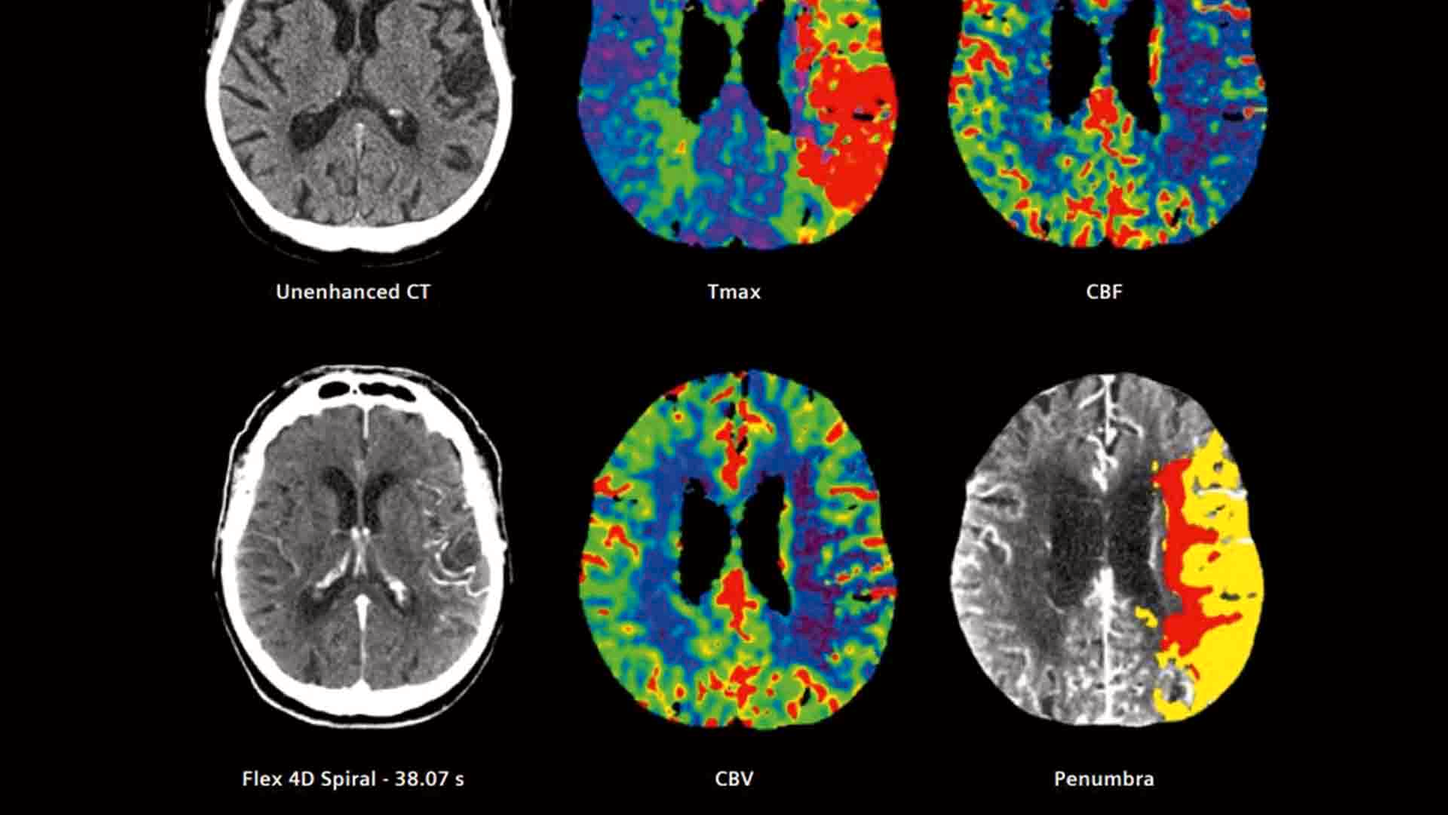

Application Training for Computed TomographyCourse overview - explore our offerings

These courses are offered as classroom training in our Training Centers or as as virtual classroom training independently where you are located. Theoretical principles of imaging are supplemented by a wide range of practical exercises, giving you the opportunity to gain skills for day-to-day clinical work. In our virtual courses we impact practical knowledge in clear, manageable units and focus on retaining the interactive approach that you are familiar with from our face-to-face training. Learn in the virtual work space and benefit from innovative digital methods.